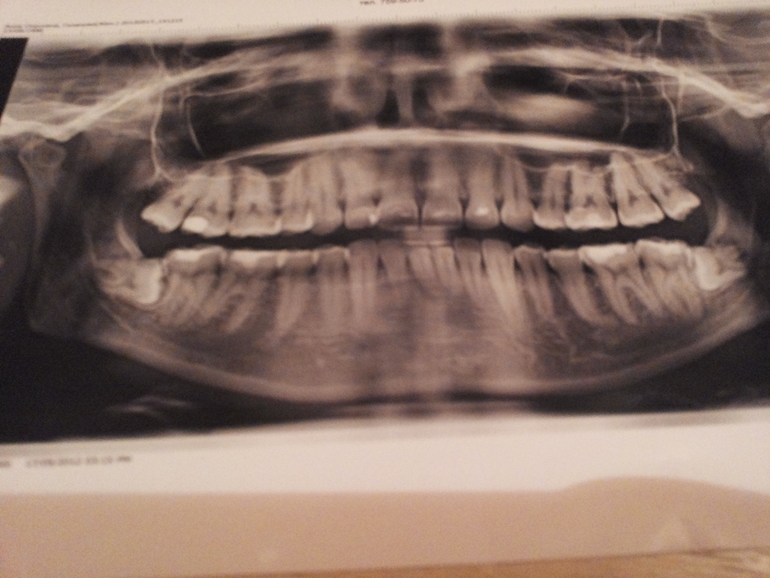

Дочь взялась за лечение зубов, кариес, удаление нерва - делали снимок и увидели ужас-ужасный. У неё зачатки зубов мудрости с обоих сторон находятся в горизонтальном положении! Т.е. если, не дай Бог, они начнут расти...даже думать страшно.

Ничего в этом страшного нет. У меня такое же:

Мнений по поводу удаления много выслушала: удалять, не удалять, удалить один (т.к. другой под костью и придется её резать). Мне они вообще не мешали, у нас это генетическая особенность. Единственное мне после брекитов они подпортили немного зубик из ряда выбили, но этого вообще не заметно и можно сам уголок зуба подпелить. А так лежат себе и никуда не двигаются. Нынешняя врач вообще сказала: скучно жить и здоровья не жалко- удаляй... Обычно их удаляют когда они начинают болеть, тогда и сами захотите избавиться. Странно, что врачи так сразу- ужас ужасный (видимо в интересах, сами понимаете каких). Сходите ещё в клинику, выслушайте мнение. Посоветовать могу http://medbooking.com/clinic/dentaspa - Дента Спа, другие мнения не повредят вам.